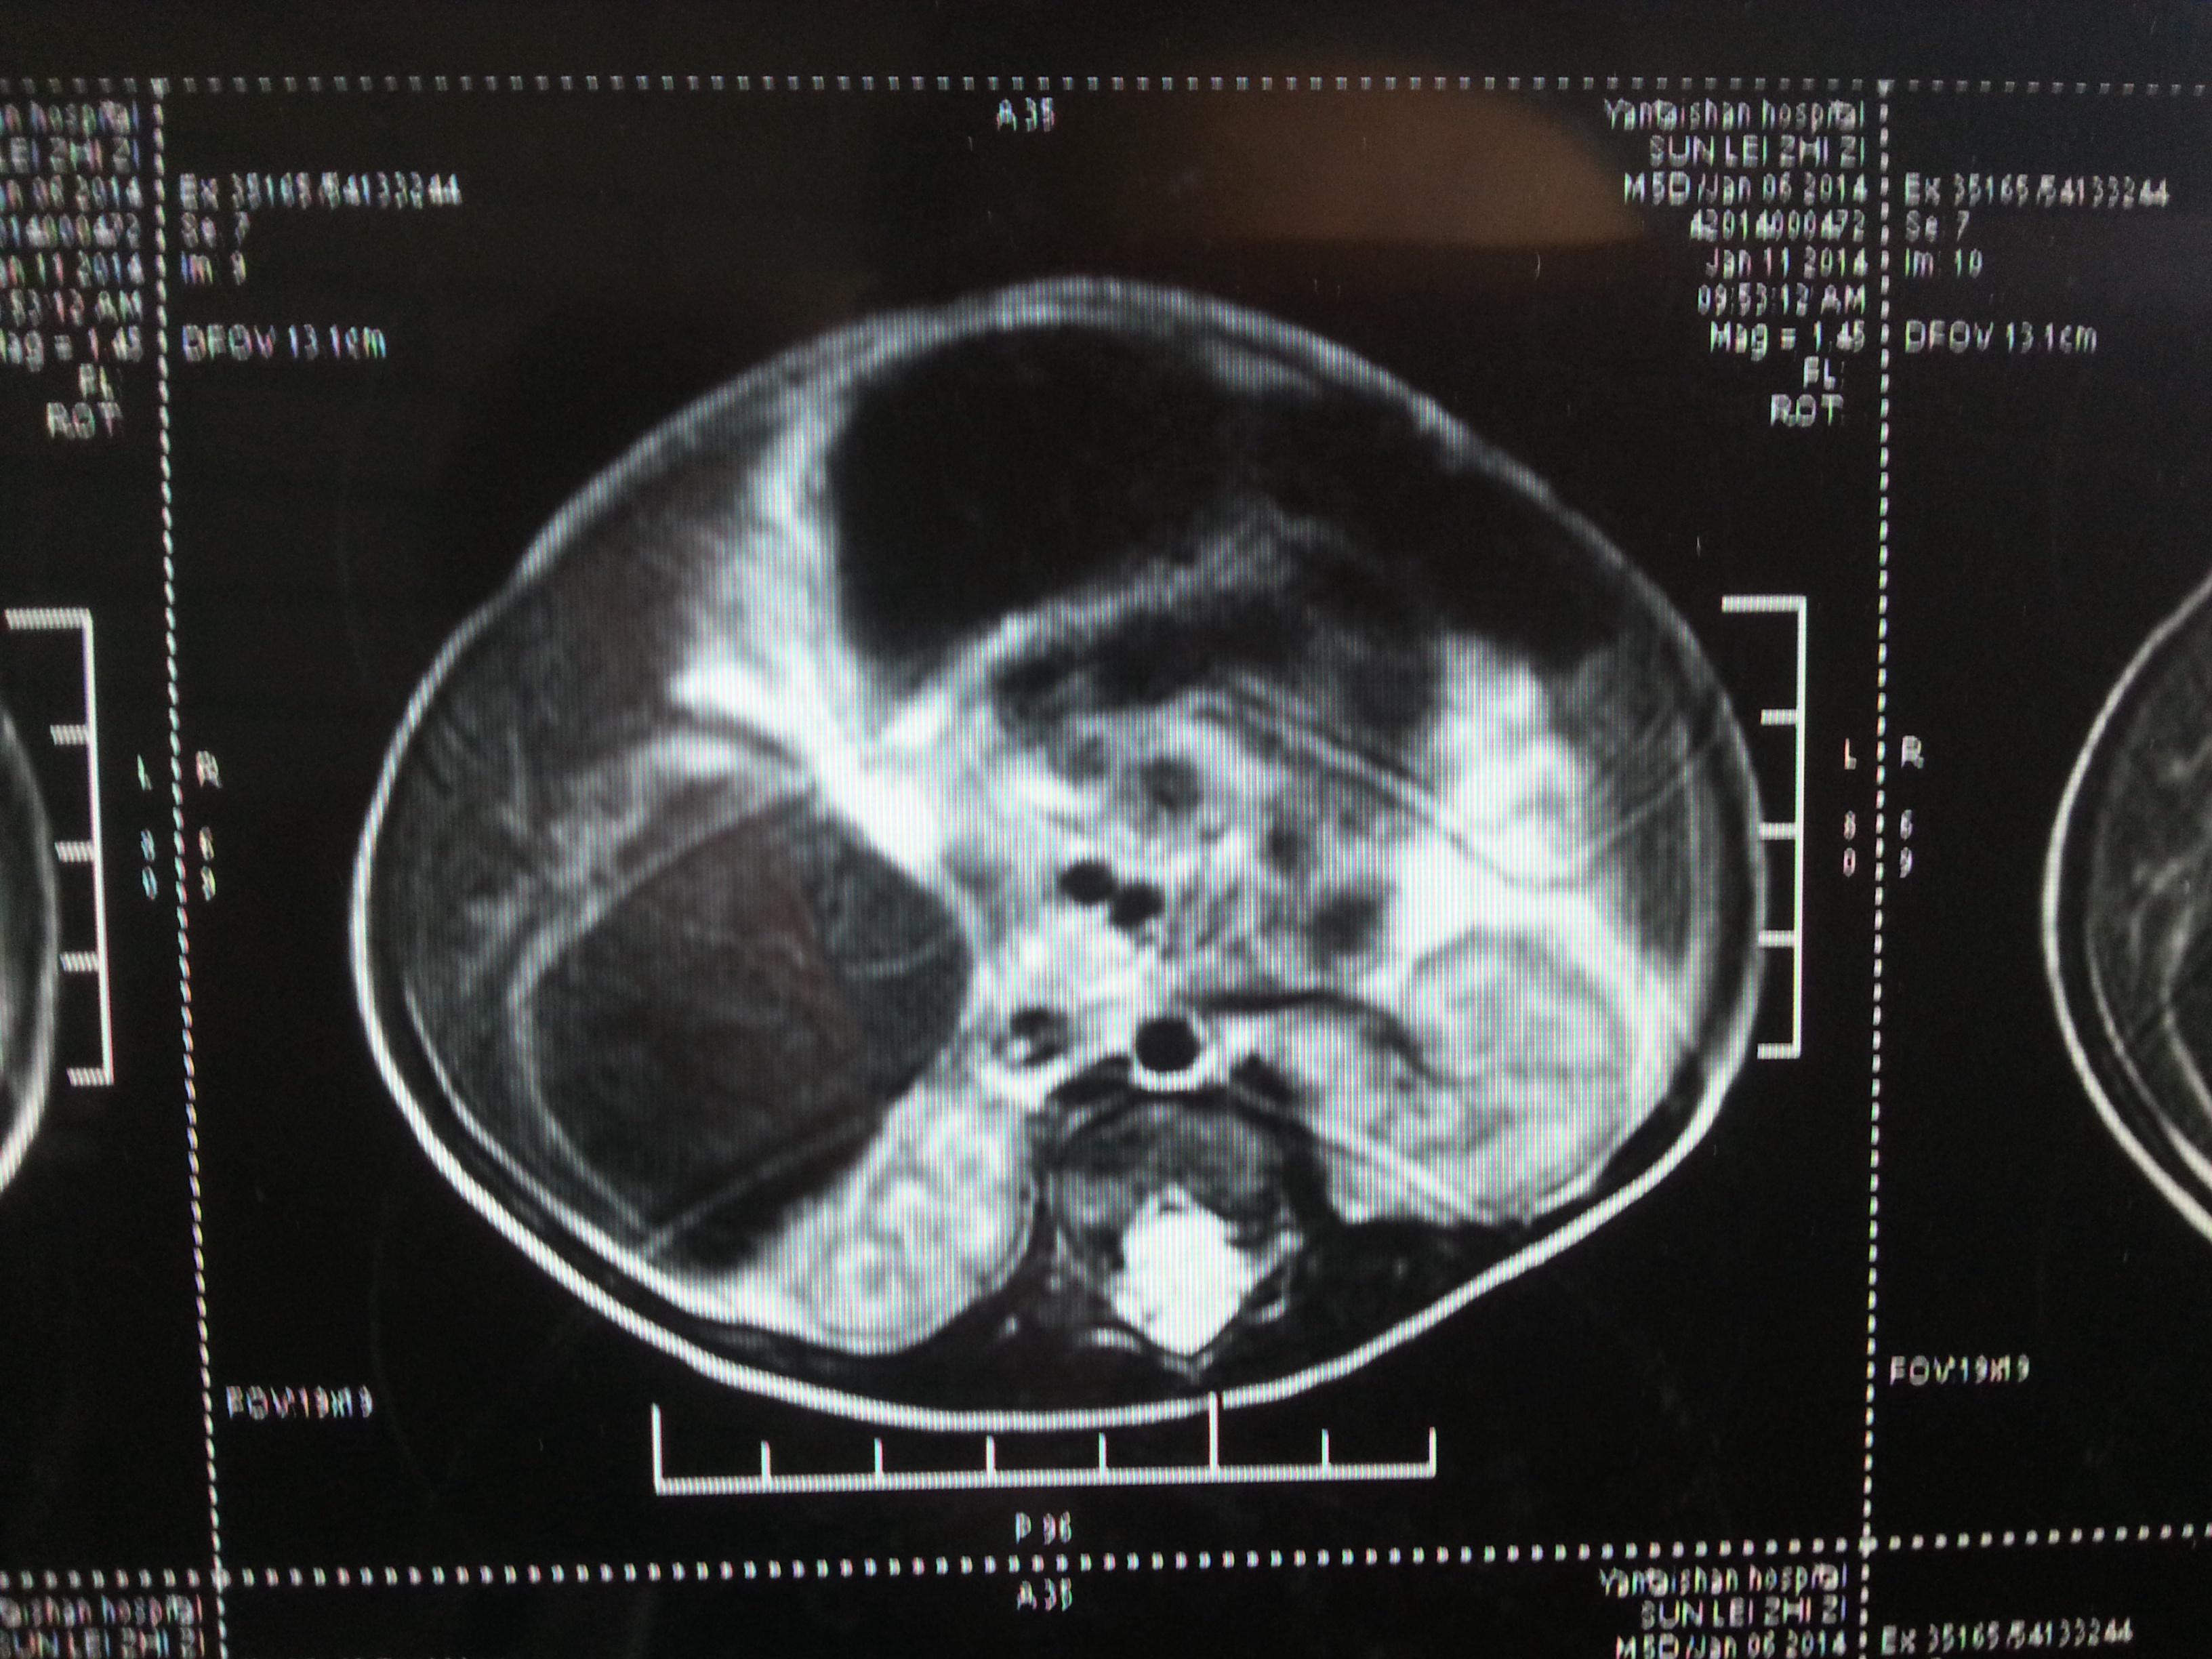

孕期这4项检查又麻烦又揪心,你经历到第几项了?如果宝宝的这项数据在3毫米以下,属于正常现象,如果大于3毫米,则属于异常情况,虽然这项检查不需要憋尿,也可以放心吃早餐,但是也要提前预约,一旦出现问题,就会让孕妈妈十分崩溃,医生会建议再做一次进行确认,等待的时间也是非常煎熬的,这项检查做好在孕13周前做,如果拖后,过多的...